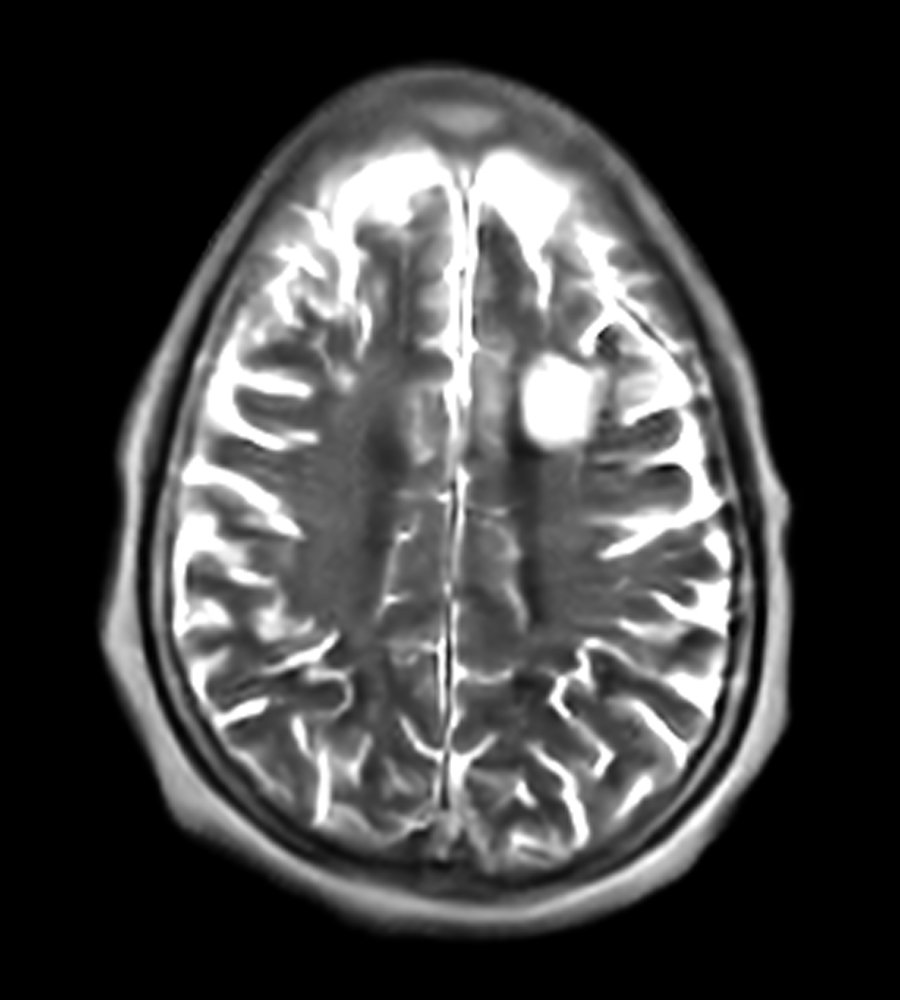

Clinical Images

Clinical Case Types: Headache, Migraine, Multiple Sclerosis, Microvascular Disease, and Tumor Routine Follow-up.

Multiple Sclerosis